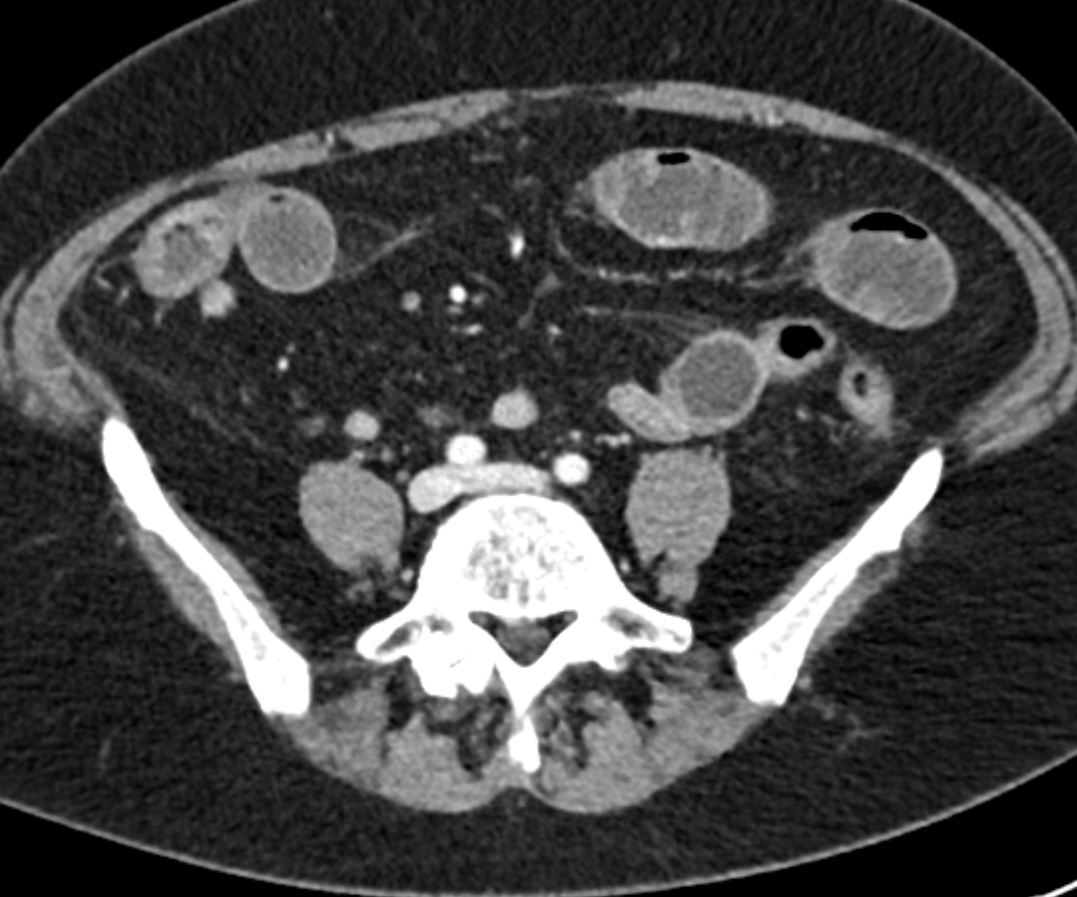

Image IQ Quiz: 59-Year-Old Patient Presents with Abdominal Pain

What is your diagnosis for this 59-year-old patient who presents with abdominal pain?

What is your diagnosis?